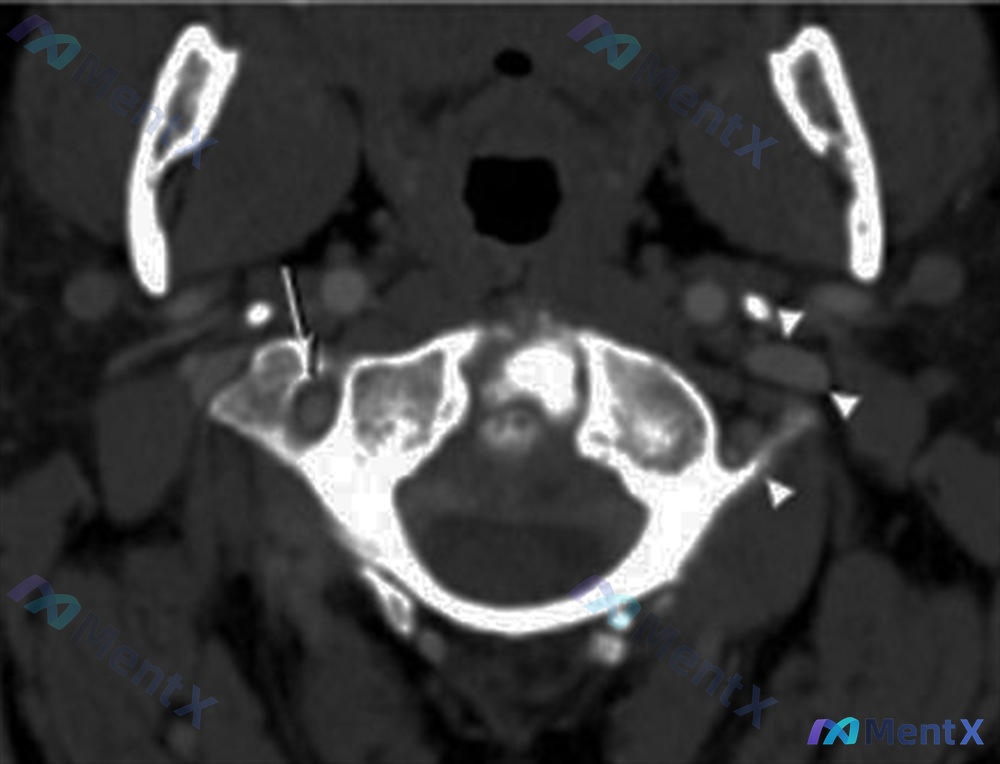

整理到一个上颈椎损伤的病例讨论材料,先看基础信息: - 患者:45岁男性 - 就诊原因:运动交通事故就诊急诊科 - 主诉:颈部疼痛 - 查体:ASIA E(神经功能完好) - 影像:张口颈椎X光片、矢状位CT、CT轴位血管造影 影像分析提示: 1. 枢椎(C2)齿状突基底部骨折,骨折块与椎体分离 2...